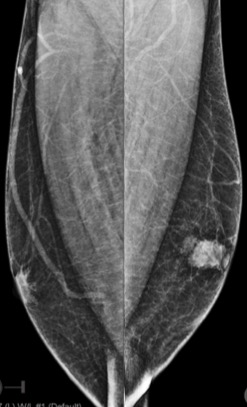

Bilateral Digital mammography , Craniocaudal (CC) and Mediolateral oblique (MLO) view revealed an irregular , high density mass with indistinct margin in retroareolar region with retracted nipple. No microcalcifications was seen. No significant axillary lymph nodes were present. Ultrasound of left breast showed an irregular, heterogeneously hypoechoic mass with indistinct margin and mild posterior acoustic enhancement, measuring about 2.5x1.9x1.3cm in retroareolar region. Internal vascularity was increased on colour doppler. On strain sonoelastogram, the mass showed increased stiffness suggestive of hard consistency. The imaging features are highly suspicious for male breast cancer and thus the mass was classified as BIRADS category 5 lesion and Ultrasound guided biopsy was advised. Patient underwent left modified radical mastectomy and final histopathological report was Invasive Lobular carcinoma. No nipple or lymphovascular invasion was identified.

The imaging features are highly suggestive of male breast cancer and thus the mass was classified as BIRADS category 5